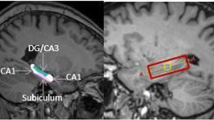

Considerable evidence in animals demonstrates the importance of the hippocampus in HPA axis modulation (Jacobson and Sapolsky 1991). Hippocampal lesions are associated with hypersecretion of glucocorticoids during stress-induced activation of the HPA axis (Feldman and Weidenfeld 1991; Feldman and Conforti 1976; Slusher 1966; Wilson et al. 1980; Fischette et al. 1980; Kim and Kim 1961; Knigge and Hays 1963; Moberg et al. 1971; Feldman and Conforti 1980), whereas stimulation of the hippocampus inhibits the adrenocortical stress response (Bouille and Bayle 1973; Rubin et al. 1966; Mandell et al. 1962; Slusher and Hyde 1961). Stimulation of the CA3 region dentate and subiculum appears to increase corticosteroid levels while CA1 stimulation decreases corticosterone levels in rats (Dunn and Orr 1984), suggesting both positive and inhibitory effects of different hippocampal regions on the HPA axis.